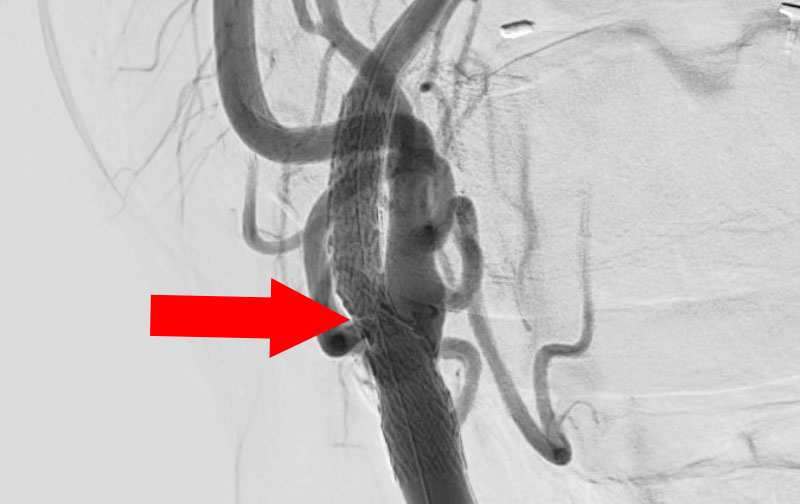

1333

'23年1月23日

右頚部内頚動脈狭窄症

70代

院内外来